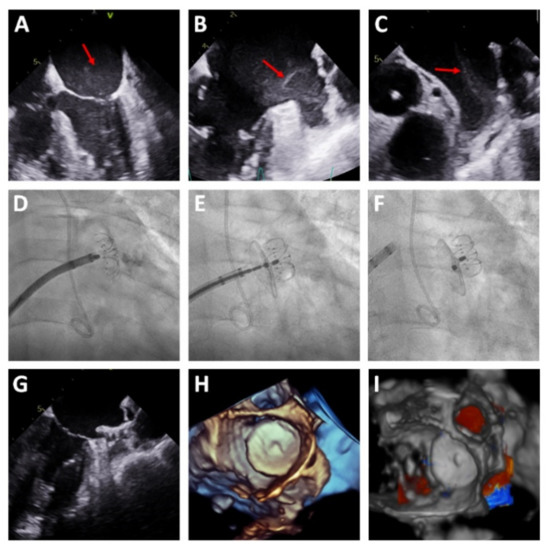

Figure 1. Case of left atrial appendage closure (LAAC) with the LAmbre™ device showing the resistance of the device to direct impact from a severe regurgitation jet from a mitral periprosthetic leak. Legend: (AC) device implantation. (D,E) transesophageal echocardiography (TEE) showing a regurgitation jet from the leak toward the device, flowing between the cover disk and the umbrella (red arrow). (F,G) 3D model for planning of the percutaneous closure of the leak (red arrow). (H) Percutaneous closure of the leak with a 14 × 5 mm Amplatzer Vascular Plug III device (Abbott Vascular, USA) (white arrow). (I) TEE confirming the correct implantation of the device (white arrow) with no interference with the LAAC system or with the cusps of the mitral bioprosthesis, reducing the regurgitation to mild.